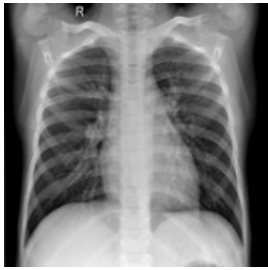

Second: the performance metrices for the proposed edge detection technique is measured for infected sample images using MATLAB and Zynq702 FPGA. The results of these performances are shown in Table 3.

Table 2 and Table 3 illustrate both the healthy and infected images, respectivly, the clarity of edges is observed. The tables indicate that using the proposed method with MATLAB led to a significant improvement in edge clarity in the Infected images compared to the healthy ones. This is due to the characteristics of the COVID-19 disease present in the infected images, which increase the complexity of the edges and make them less clear. They also indicate that the images produced by the proposed method are clearer than those from MATLAB, as the proposed method employs fixed-point arithmetic to represent numbers that are closer to edge values than the numbers used by MATLAB, which relies on floating-point arithmetic.

Table 3. Results for COVID-19 infected images

Input Image

MATLAB Result

FPGA Result